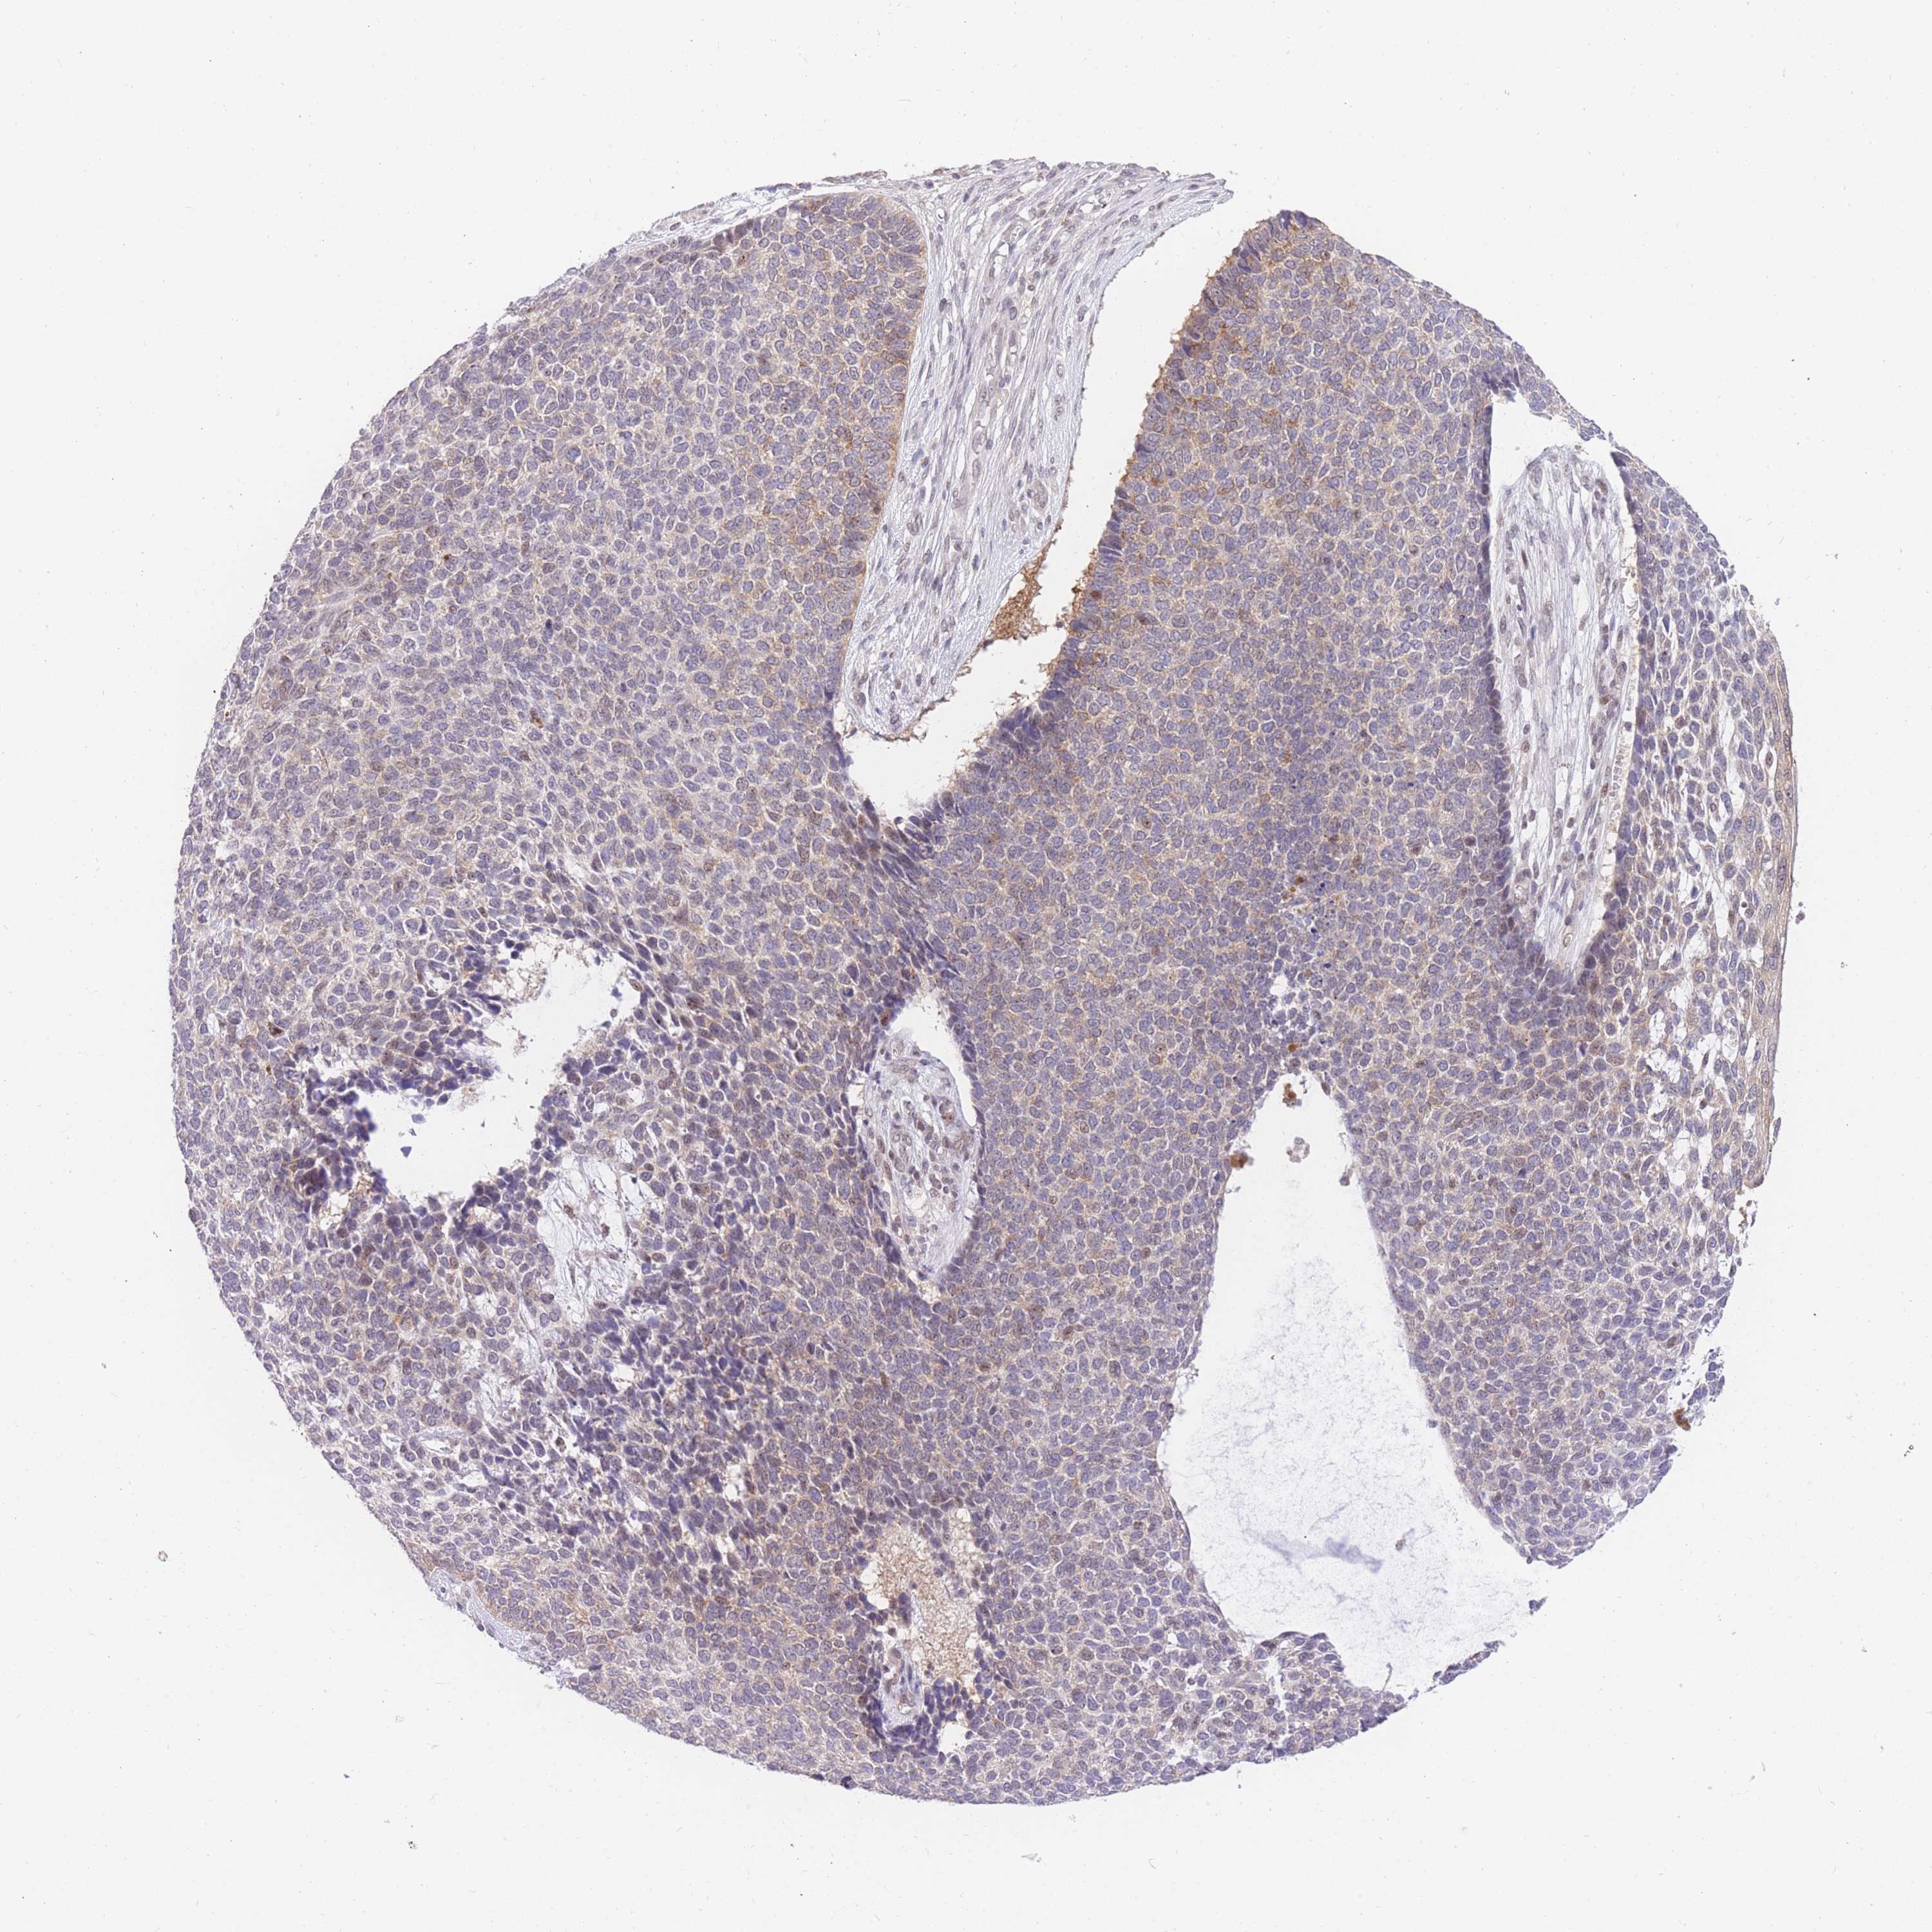

SKIN CANCER - Protein expressioni

A mouse-over function shows sample information and annotation data. Click on an image to view it in a full screen mode. Samples can be filtered based on level of antibody staining by selecting one or several of the following categories: high, medium, low and not detected. The assay and annotation is described here.

Each image is clickable and will lead to virtual microscopy that enables deeper exploration of all samples and also displays staining intensity scores, fraction scores and subcellular localization as well as patient and tissue information for each sample.

Antibody HPA061803

Basal cell carcinoma